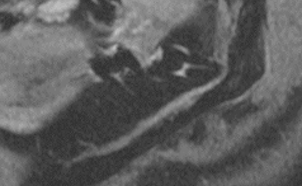

Sollte es zu einer Schädigung des Nervus alveolaris inferior oder des Nervus lingualis gekommen sein, wie in dem Bildbeispiel durch Fehlpositionierung eines dentalen Implantats durch den Mandibularkanal, lässt sich der Nervenschaden durch MRT direkt darstellen und graduieren. Somit kann schnellstmöglich eine Diagnose gestellt und Therapieoptionen evaluiert werden.

Diese direkte Form der Nervendarstellung ist nur durch MRT möglich. Insbesondere vor komplizierten Weisheitszahnentfernungen ist auch eine prophylaktische Darstellung der Lagebeziehung des Nervus alveolaris inferior zu verlagerten Weisheitszähnen sinnvoll.